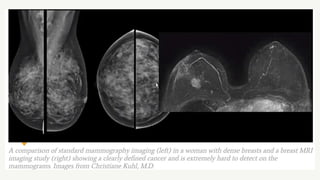

• 65% in dense breasts

Ultrasound screening

➢High risk population

➢Young women with mammographically

dense breasts

MRI SCREENING

• HIGH sensitivity: 70-100%